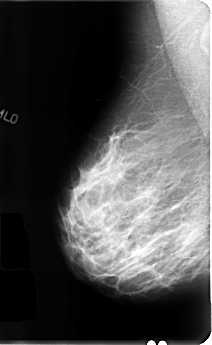

ics_version 1.0 filename B-3111-1 DATE_OF_STUDY 23 7 1996 PATIENT_AGE 44 FILM FILM_TYPE REGULAR DENSITY 3 DATE_DIGITIZED 22 1 1998 DIGITIZER LUMISYS LASER SEQUENCE LEFT_CC LINES 4888 PIXELS_PER_LINE 2856 BITS_PER_PIXEL 12 RESOLUTION 50 OVERLAY LEFT_MLO LINES 4864 PIXELS_PER_LINE 3040 BITS_PER_PIXEL 12 RESOLUTION 50 OVERLAY RIGHT_CC LINES 4792 PIXELS_PER_LINE 2880 BITS_PER_PIXEL 12 RESOLUTION 50 NON_OVERLAY RIGHT_MLO LINES 4824 PIXELS_PER_LINE 2960 BITS_PER_PIXEL 12 RESOLUTION 50 NON_OVERLAY |